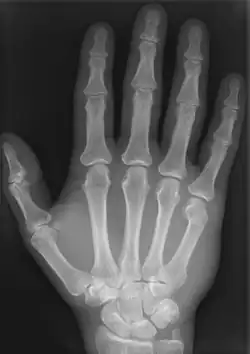

Przykładowe zdjęcia rentgenowskie

Zdjęcie rentgenowskie dłoni Alberta von Köllikera wykonane przez Röntgena w Physikalisches Institut Uniwersytetu w Würzburgu 23 stycznia 1896 r.[8]